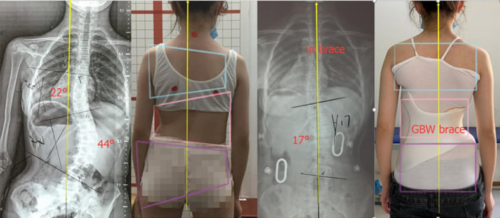

1. زاوية كوب (Cobb Angle)

يوفر الحزام الجديد فوائد إضافية في تحسين المظهر الخارجي للجسم.

2. تماثل الجذع وشكل الظهر

كانت الفروقات واضحة عند قياس تأثير الحزام على شكل الجسم:

الحزام الجديد حسّن شكل سطح الظهر بنسبة 49.6٪، وهو تحسن ملحوظ.

في المقابل، شهد مستخدمو الحزام التقليدي تدهورًا بنسبة 6.8٪ في شكل الظهر.

التماثل العام للجذع تحسن بنسبة 30٪ مع الحزام الجديد، بينما ازداد سوءًا بنسبة 2.2٪ لدى مستخدمي الحزام التقليدي.

وهذا يدل على أن استخدام القياسات ثلاثية الأبعاد يعزز التماثل العام للجسم بشكل واضح.